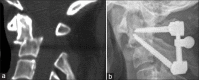

Background: There are several techniques for treating atlantoaxial instability, including the Magerl transarticular screw fixation and the Harms/Goel C1-C2 screw rod techniques. Here, we present a novel technique utilizing a polyaxial screw rod system and a combination of C1 lateral mass and C1-C2 transarticular screws.

Conclusions: C1 lateral mass and C1-C2 transarticular polyaxial screw rod fixation techniques were effective in achieving immediate rigid immobilization of the C1-C2 motion segment.